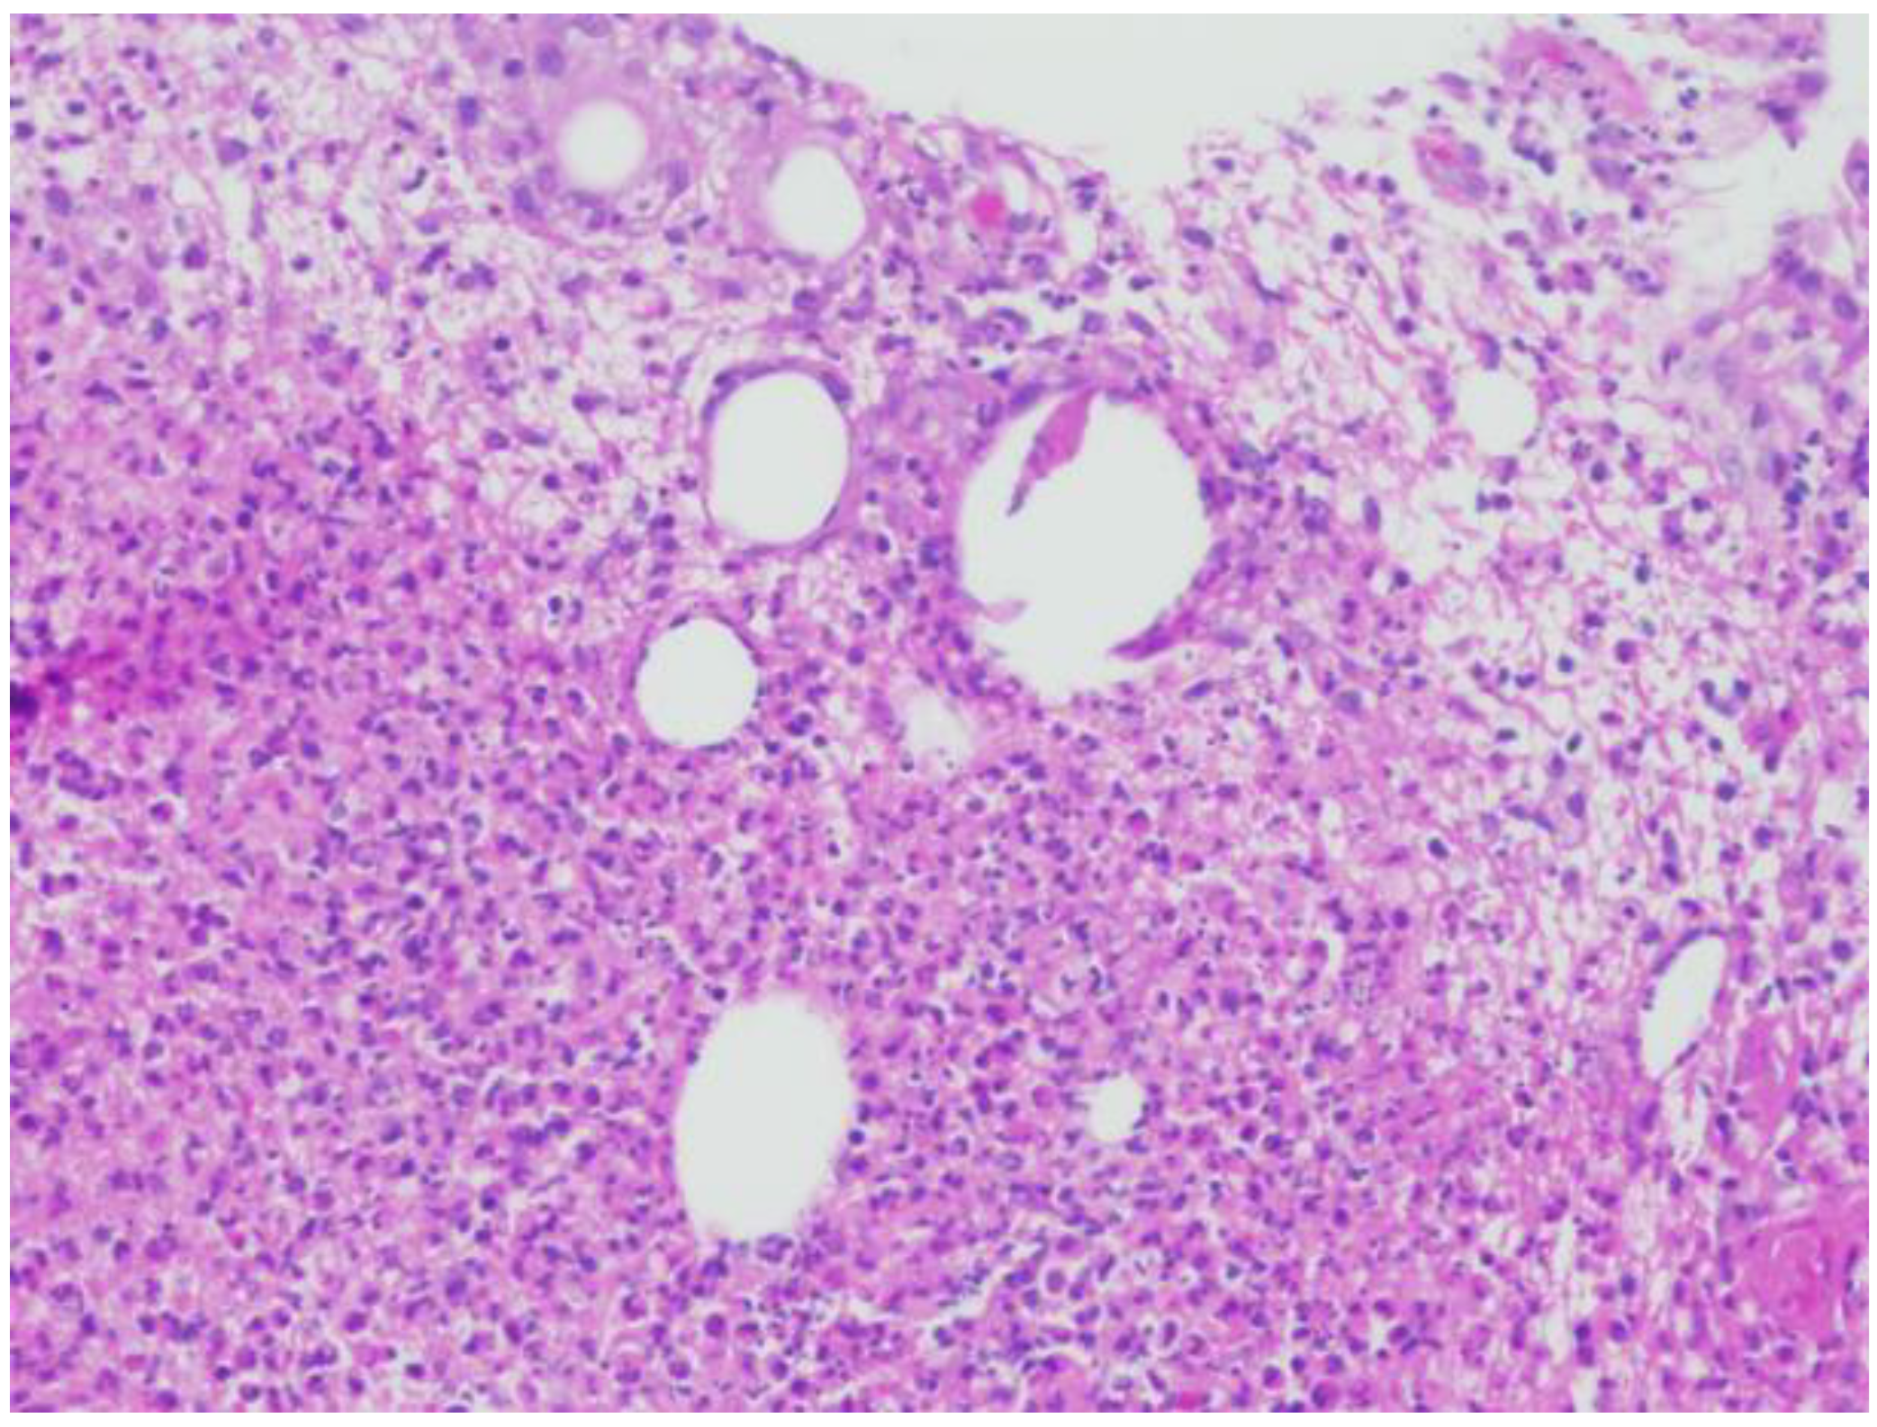

A 38-year-old female with Fitzpatrick type III skin presented to the dermatology clinic with a tender, warm, erythematous 5 cm plaque on the left breast. She was evaluated for both infectious and malignant processes with fine-needle aspiration, two-punch biopsies, and tissue culture. Histologically, her biopsies demonstrated numerous focally necrotic granulomata with negative fungal, acid-fast bacterial, and Gram stains (Figure 1) At that time, a diagnosis of CNGM was made. Treatment initially consisted of doxycycline 100 mg twice daily and oral prednisone. Despite prolonged courses of prednisone, her disease was not controlled with tapering to doses lower than 40 mg daily.

Figure 1. Hematoxylin and eosin staining at 20× magnification, showing cystic spaces with granulomatous inflammation and mixed neutrophilic and lymphohistiocytic inflammation.

CNGM is further characterized (and differentiated by some sources from IGM) by suppurative lipogranulomas, which consist of acute to chronic granulation tissue, with central lipid vacuoles surrounded by neutrophils. Additional inflammatory cells can also be present, including eosinophils, histiocytes, and multinucleated giant cells. Necrosis may be focally present but is not a defining feature. Within these spaces, lipophilic Gram-positive Corynebacterium (e.g., C. kroppenstedtii) species are commonly reported [4].

CNGM consists of lipogranulomas that have central lipid vacuoles surrounded by neutrophils, and an outer cuff of epithelioid histiocytes [3]. Of note, the surrounding infiltrates consists of Langhans-type giant cells, lymphocytes, and neutrophils [3]. These lipid vacuoles may sometimes have rod-shaped Gram-positive bacilli [3]. These bacteria, also termed “diphtheroids” are aerobic (and facultative anaerobic), catalase-positive, asporogenous, nonmotile, club-shaped bacilli that lack the mycolic acid production of other Corynebacterium species [5]. One study found that performing 6 µm thick section Gram stains of representative tissue blocks enhances detection rates and facilitates identifying Gram-positive bacteria in CNGM [8].